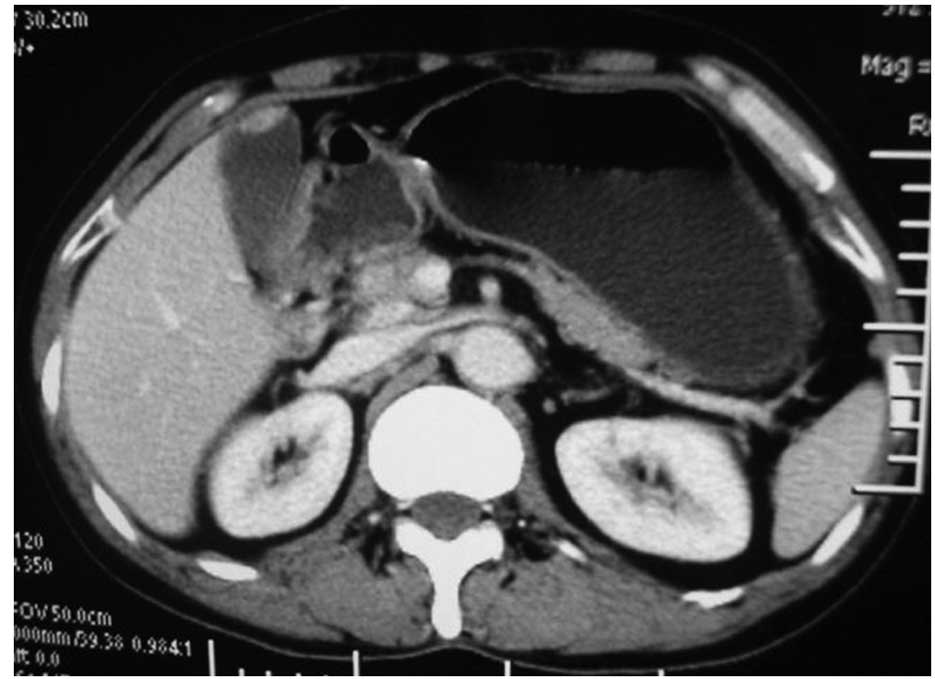

Pyonephrosis As A Sign Of sarcomatoid carcinoma Of The Renal ...

Pyonephrosis as a sign of sarcomatoid carcinoma of the renal pelvis Sergio Fernández-Pello, Victoria Venta, Iván González, lial carcinoma and is linked with a bad prognosis. In the same sample, zones of epithelial carcinoma, adenocarci- ... Content Retrieval